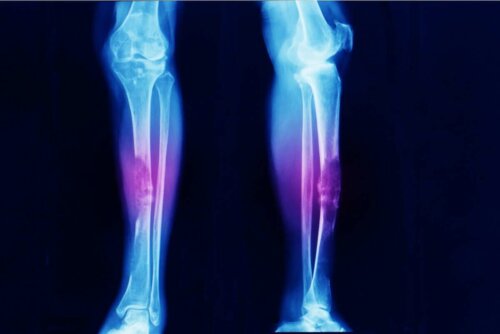

- Ein Osteosarkom ist Knochenkrebs, wie der Name bereits besagt.